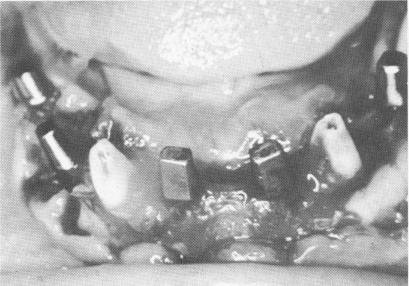

Fig. 13-59. A, Endodontic stabilizers were introduced into the cuspids. The teeth and implants are protected from the saliva with the use of rubber dams. B, An immediate postoperative radiograph.

1 Four blade implants tapped into mandibular arch

2 Rubber dams used while endodontic stabilizers introduced into cuspids